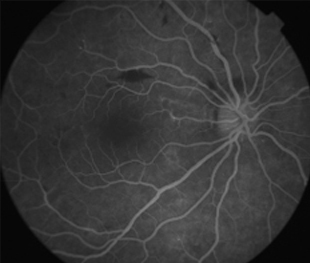

Angiografía OI

- Angiografía: teñido arterial, escape capilar, más tardíamente, no perfusion arteriolar y venular con teñido de las paredes vasculares y dilatación venosa.